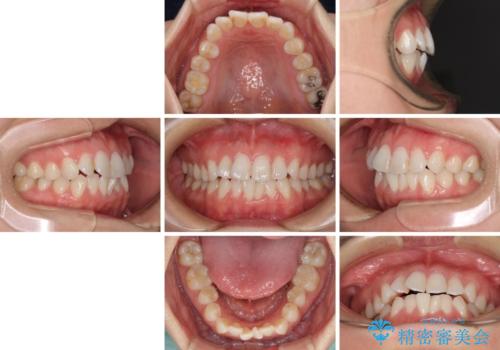

- ワイヤーではない矯正治療があると聞いたとのことで来院された患者様です。

長年前歯のデコボコを気にしていたもののワイヤー矯正に抵抗があり躊躇していたそうですが、インビザラインなら治療してみたいとのことで相談にいらっしゃいました。

インビザライン適用の歯列であったため、歯と歯の間を削るIPRを用いて改善することとしました。